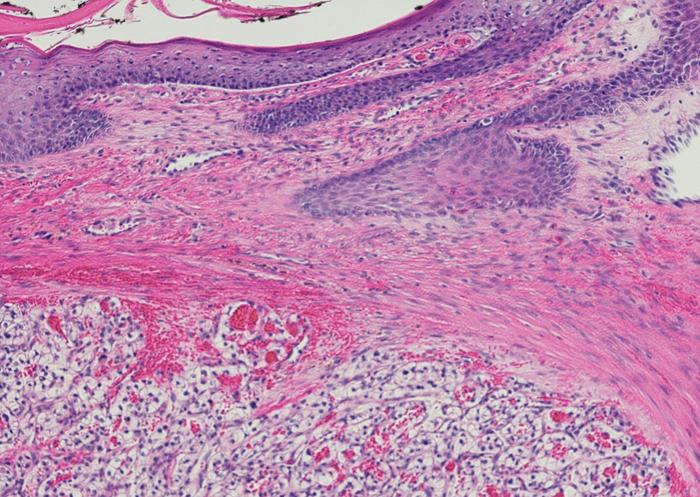

Highly aggressive cell carcinomas

image:

Mathematics, histopathology and genomics converge to confirm that highly aggressive clear cell renal cell carcinomas display low levels of intratumour heterogeneity.

Professor Laruelle has used this game to analyse bilateral cell interactions in highly aggressive clear cell renal cell carcinoma in two different scenarios: one involving low tumour heterogeneity, when only two tumour cell types compete for a resource; and the other, high tumour heterogeneity, when such competition occurs between three tumour cell types. Clear cell renal cell carcinoma is so named because the tumour cells appear clear, like bubbles, under the microscope. This type of carcinoma has been taken as a representative case for the study, as it is a widely studied paradigm of intratumour heterogeneity (which refers to the coexistence of different subpopulations of cells within the same tumour).